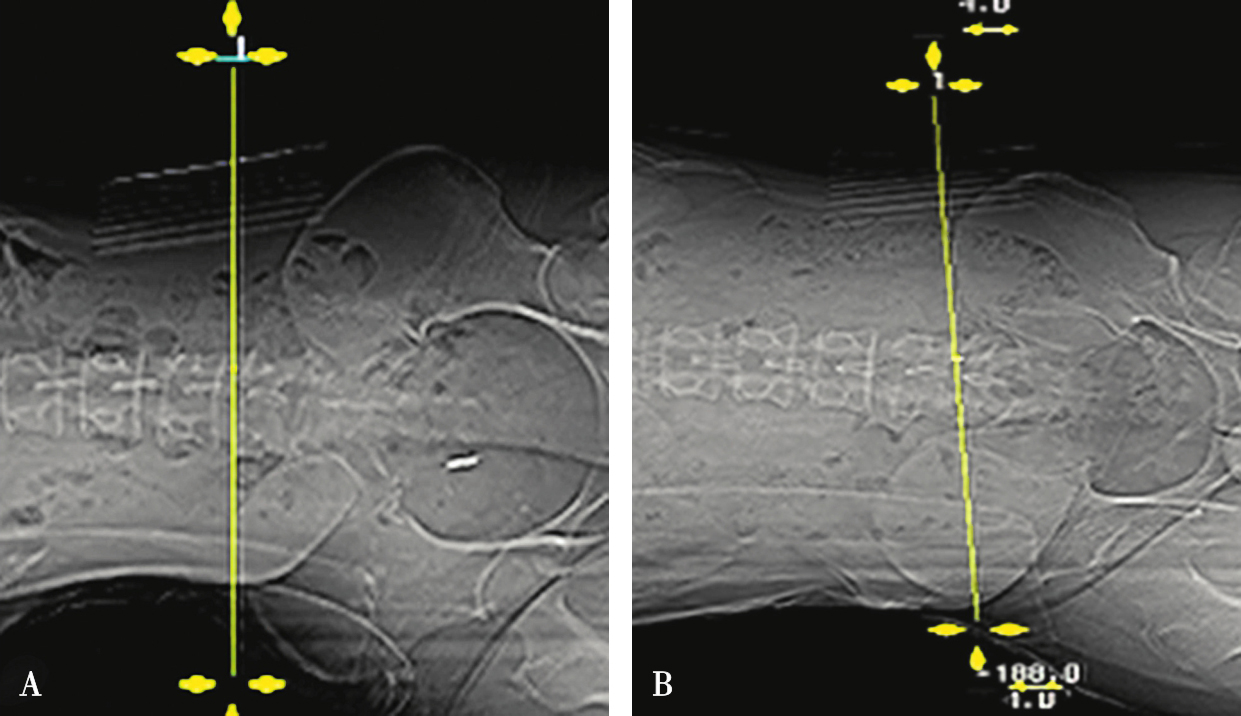

在扫描产生的多层横断面中选择出最符合穿刺要求的一层,作为设计入路和引导穿刺定位的操作平面,我们将该层称为“靶点操作平面”。根据不同的手术目的选择该平面的要求也不同:避骨入路类手术如经椎板间入路椎间盘靶点定位类,应选择具有最大程度避开神经、血管、脏器、骨质而到达靶点的平面,如图3-3-12中显而易见图B是最合适的平面;经椎间隙侧方入路时的扫描图像中(图3-3-13),图B最合适;而经骨入路类手术如经皮椎体骨折复位外固定、椎体成形术等,应选择椎弓根宽大处的平面,如图3-3-14中图B作为操作平面最合适。CT机架角度扫描的横断位平面自然也是倾斜的,而穿刺定位入路是在该平面内的,因此存在如下关系:CT机架扫描角度=靶点操作平面角度=定位针穿刺时的头足倾斜角度(图3-3-15)。

图3-3-12 L 5 /S 1 经椎板间隙入路-不同层面横断位像

A.靶点偏头侧平面;B.靶点操作平面;C.靶点偏足侧平面

图3-3-13 L 4/5 侧方入路-不同层面横断位像